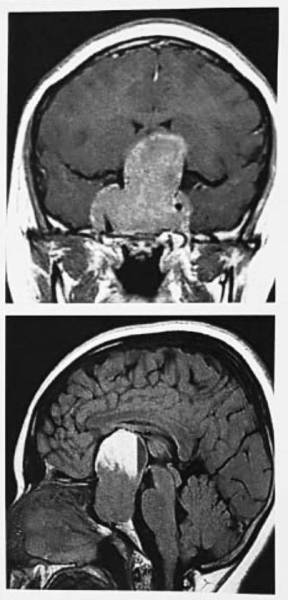

وأوضحت الإدارة الطبية أن المريضة أحيلت إلى مركز العلوم العصبية بالمدينة الطبية بعد فقدان شبه كامل للإبصار في العين اليسرى وضعف شديد في العين اليمنى بسبب وجود ورم ضخم ونازف في الدماغ في الغدة النخامية وضاغط على أعصاب العين، وتم التعامل معها في وقت وجيز والاستعانة بكافة الفرق الطبية من استشاريي جراحة مناظير الأنف والجيوب الأنفية وتخدير الأعصاب وطب العيون والغدد الصماء والعناية الحرجة وجراحي المخ والأعصاب.

وأجريت كافة الفحوص اللازمة من قبل استشاريي أشعة الأعصاب، حيث أجرى الفريق الطبي تدخلا جراحيا عاجلا من فريق مكون من استشاري جراحة المخ والأعصاب وقاع الجمجمة الدكتور محمد غازي عبده واستشاري جراحة الأنف والأذن والحنجرة الدكتور إسلام حرز الله، حيث تم استئصال الورم وتخفيف الضغط عن عصب العين في عملية استغرقت 7 ساعات تكللت بالنجاح التام.